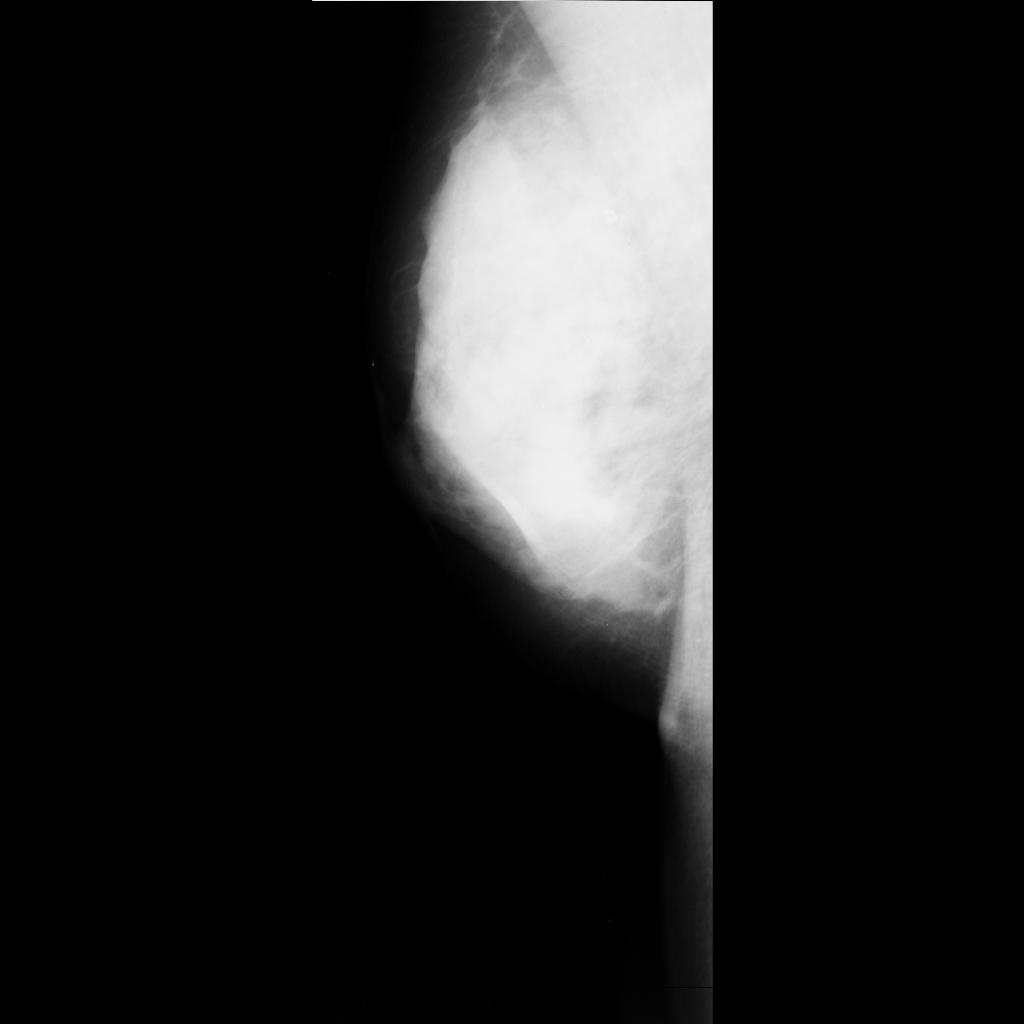

benign

malignant